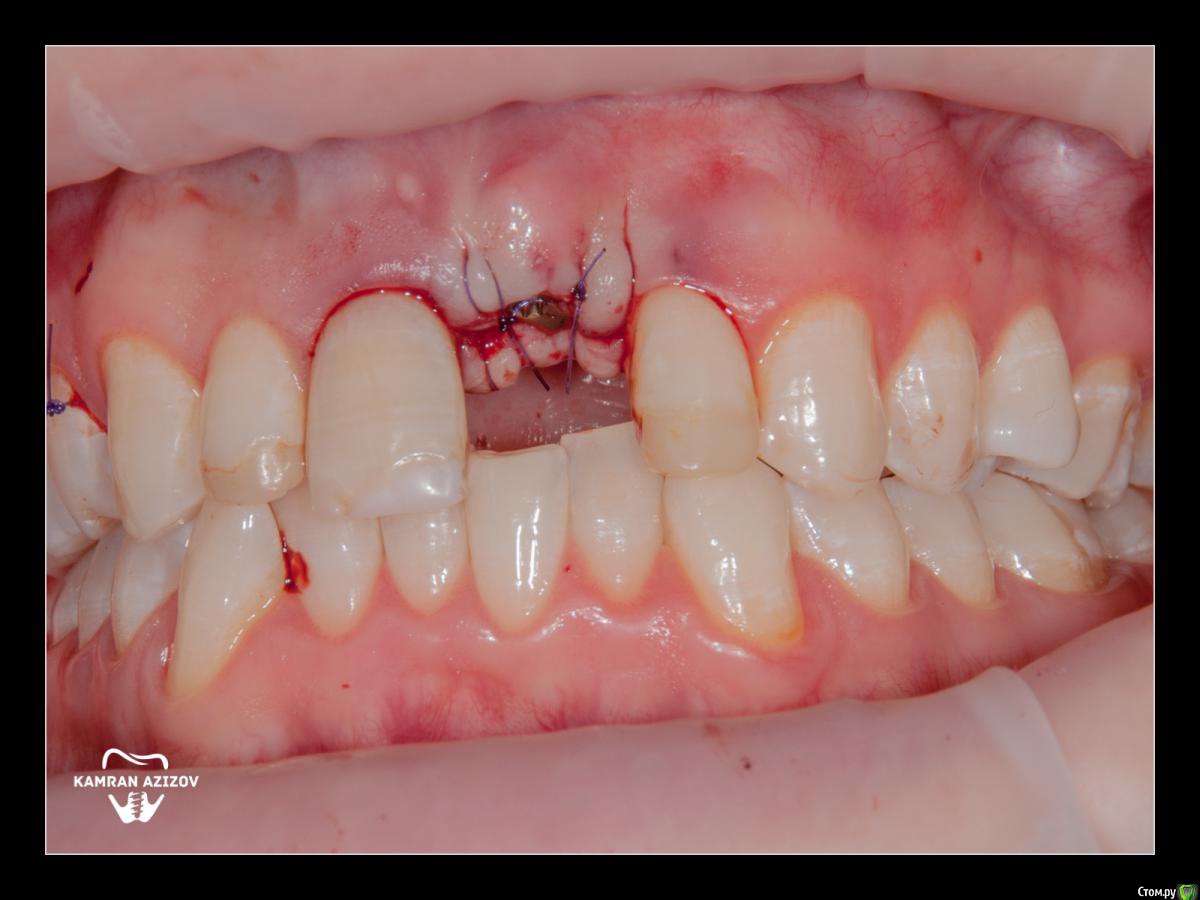

Dman Опубликовано 11 октября, 2019 Поделиться Опубликовано 11 октября, 2019 На 9 фото не понятно что, другой формирователь и корректировал десну? Ссылка на комментарий

kamranchick Опубликовано 11 октября, 2019 Автор Поделиться Опубликовано 11 октября, 2019 На 9 фото не понятно что, другой формирователь и корректировал десну?да. это такой формирователь на штраумане который винтом прикручивается, денег не было на времянку, пришлось поставить такой формик Ссылка на комментарий

Dman Опубликовано 11 октября, 2019 Поделиться Опубликовано 11 октября, 2019 да. это такой формирователь на штраумане который винтом прикручивается, денег не было на времянку, пришлось поставить такой формикс десной то что делали - выглядит как корректированная бором или лазером Ссылка на комментарий

kamranchick Опубликовано 12 октября, 2019 Автор Поделиться Опубликовано 12 октября, 2019 Не. Ничего особо не делал.Формик зарос. Немного освободил от мягких тканей. Чуть чуть скальпелечком прошёл и вкрутил Новый Ссылка на комментарий